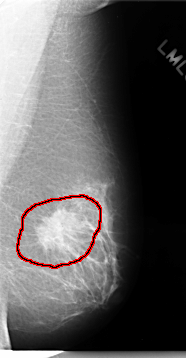

C_0075_1.RIGHT_MLO

FILE: C_0075_1.LEFT_MLO.OVERLAY

TOTAL_ABNORMALITIES 1

ABNORMALITY 1

LESION_TYPE MASS SHAPE IRREGULAR MARGINS SPICULATED

ASSESSMENT 5

SUBTLETY 5

PATHOLOGY MALIGNANT

TOTAL_OUTLINES 1

BOUNDARY